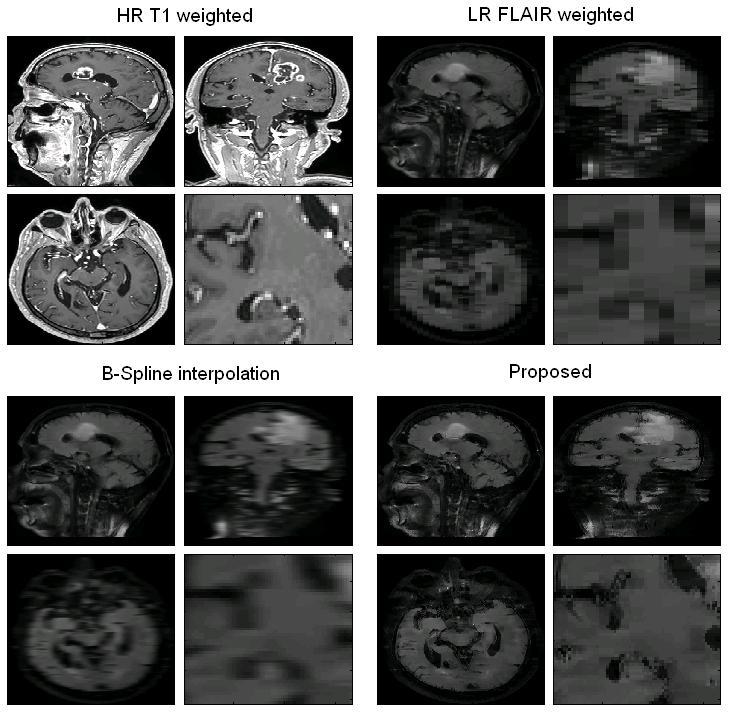

In Magnetic Resonance Imaging typical clinical settings, both low and high resolution images of different types are routinarily acquired. In some cases, the acquired low resolution images have to be upsampled to match with other high resolution images for posterior analysis or postprocessing such as registration or multimodal segmentation. However, classical interpolation techniques are not able to recover the high frequency information lost during the acquisition process. In the present paper, a new superresolution method is proposed to reconstruct high resolution images from the low resolution ones using information from coplanar high resolution images acquired of the same subject. Furthermore, the reconstruction process is constrained to be physically plausible with the MR acquisition model that allows a meaningful interpretation of the results. Experiments on synthetic and real data are supplied to show the effectiveness of the proposed approach. A comparison with classical State-of-the-art interpolation techniques is presented to demonstrate the improved performance of the proposed methodology.